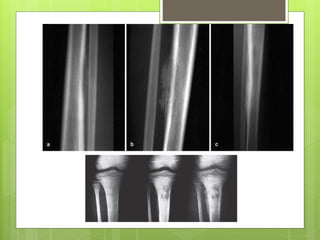

 PLAIN X-RAY

During the first week after the onset of symptoms,

 the plain radiograph shows no abnormality of the

Bone, soft-tissue swelling, but this could as well be due to a

haematoma

 or soft-tissue infection.

By the second week

 a faint extra cortical outline due to periostea new bone

formation (classic X-ray sign of early pyogenic osteomyelitis

• periosteal thickening becomes more obvious

• patchy rarefaction of the metaphysis;

 later still features of bone destruction.

 Diagnostic imaging PLAIN X-RAY During the first week after the onset of symptoms,  the plain radiograph shows no abnormality of the Bone, soft-tissue swelling, but this could as well be due to a haematoma  or soft-tissue infection. By the second week  a faint extra cortical outline due to periostea new bone formation (classic X-ray sign of early pyogenic osteomyelitis • periosteal thickening becomes more obvious • patchy rarefaction of the metaphysis;  later still features of bone destruction.